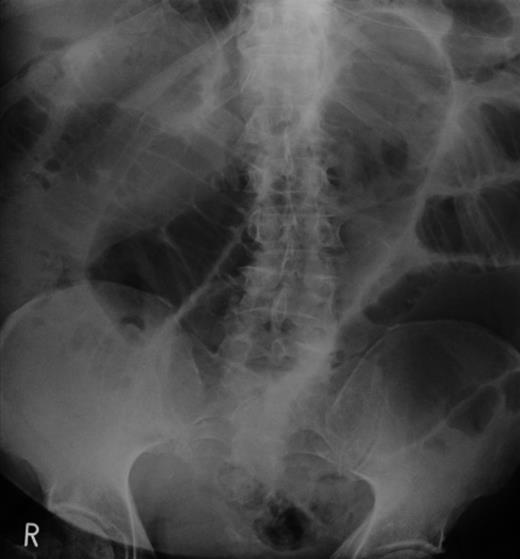

A laparotomy was performed with small bowel resection around the intussusception and primary anastomosis (Fig. 3). The excised segment included a 4-cm lesion (Fig. 4). The excised lesion was composed of areas of spindle and epithelioid cells, and immunohistochemical analysis showed positive staining with CD117, DOG1 and SMA: attributes restricted in the gut to the interstitial cells of Cajal. Genetic analysis detected an exon 11 mutation.

Current recommendations for assessing the risk of compression rely on three parameters: tumour size, location and mitotic index. In the presented case, a 4-cm maximal diameter jejunal GIST with one mitosis per high power (5 mm) field indicates a low-to-intermediate probability of metastases and 40–60% of recurrence risk [7].